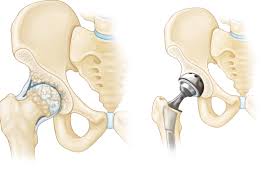

Joint pain often limits movement, reduces independence, and affects overall quality of life. Moreover, long-term joint problems gradually interfere with daily activities and emotional well-being. Joint Replacement Low Cost in Katni provides an effective solution for patients who require surgical treatment but worry about affordability.

Q2. Which joints can be replaced at low cost?

Knee, hip, and other major joints can be replaced depending on medical condition.